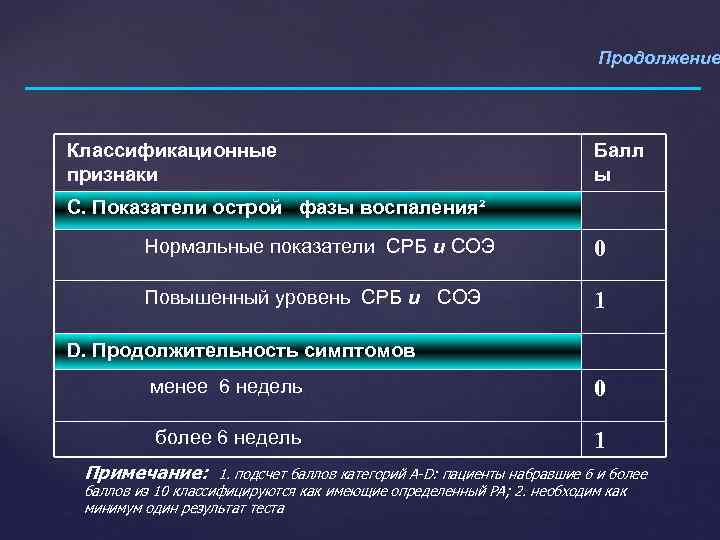

Продолжение Классификационные признаки Балл ы С. Показатели острой фазы воспаления² Нормальные показатели СРБ и СОЭ 0 Повышенный уровень СРБ и СОЭ 1 D. Продолжительность симптомов менее 6 недель 0 более 6 недель 1 Примечание: 1. подсчет баллов категорий А-D: пациенты набравшие 6 и более баллов из 10 классифицируются как имеющие определенный РА; 2. необходим как минимум один результат теста

Продолжение Классификационные признаки Балл ы С. Показатели острой фазы воспаления² Нормальные показатели СРБ и СОЭ 0 Повышенный уровень СРБ и СОЭ 1 D. Продолжительность симптомов менее 6 недель 0 более 6 недель 1 Примечание: 1. подсчет баллов категорий А-D: пациенты набравшие 6 и более баллов из 10 классифицируются как имеющие определенный РА; 2. необходим как минимум один результат теста